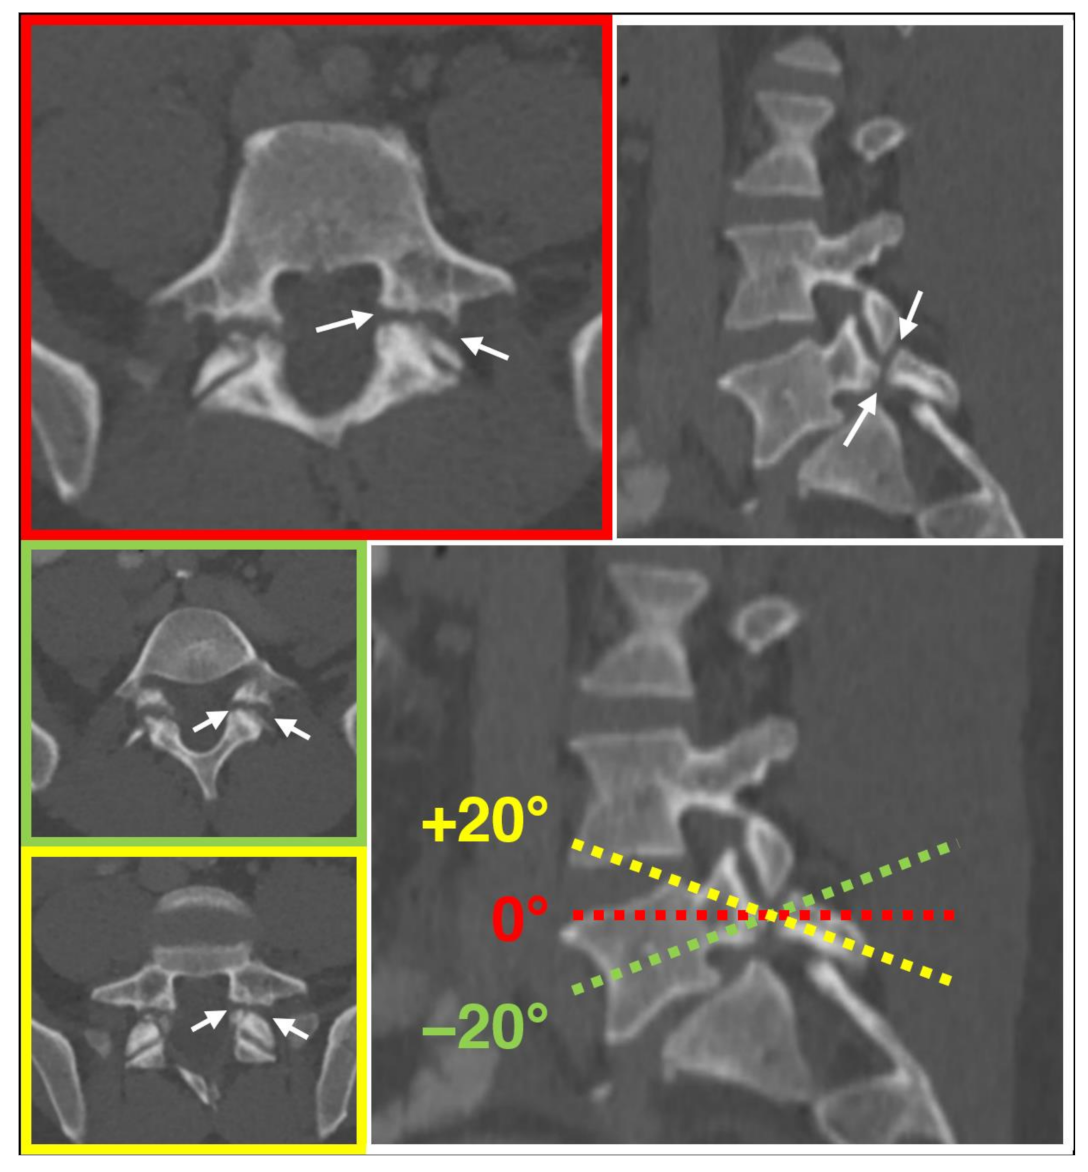

One resident radiologist (F.A.H.), supervised by an expert radiologist (H.A.), investigated the presence of the aforementioned three imaging features in one case each of “spondylolysis” and “degenerative spondylolisthesis without spondylolysis”, and on one healthy spine case. Furthermore, the presence of the three criteria was tested for dependency on angulations in one case. For this, a range of +/−20° oblique tilt reconstructions were visually analyzed for the presence of the “Darth Vader sign” criteria. Tilting the perpendicular plane of the z-axis showed no relevant impact on the presence of the criteria defining the “Darth Vader sign” (Figure 2), which was identified only in the “spondylolysis” case (Figure 3).

Figure 2. Independence of the “Darth Vader sign” from plane angulation. Defects of the pars interarticularis (arrows) and the respective criteria of the “Darth Vader sign” are noted in axial (red), as well as in axial oblique of +20 (yellow) and −20 (green) degrees.